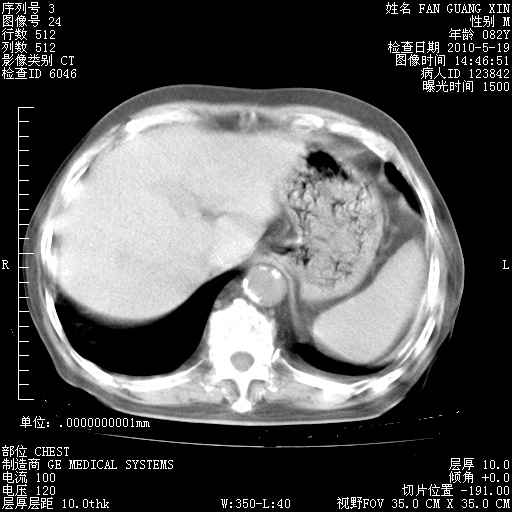

再治疗10天后的肺部CT 纵膈窗

阅读此次胸部CT,肺间质渗出性改变较入院时有吸收。目前从体温、白细胞、中性分叶明显增高,肯定存在细菌感染(发生医院感染哦,若无消化道及泌尿系统等感染的依据,肺部感染可能大)。若你院头孢哌酮舒巴坦钠耐药率较高,同意你的方案,若48小时体温仍高,可考虑使用碳青霉稀类抗菌药物,同时可予超声雾化、注意滴数时加大液体量。白蛋白33.30g/L较低哦,需加强营养等支持治疗。

从白细胞总数和中性比例看好像合并感染。肺部纹理好像比上次多,支气管炎?其他感染?